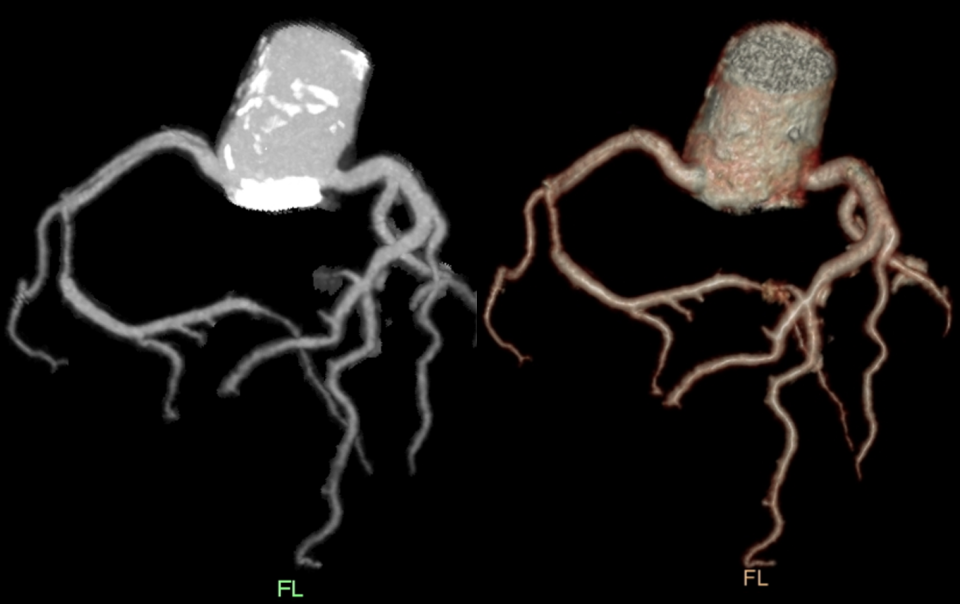

3、符合主动脉瓣及二尖瓣术后,请结合病史:男,64 岁,主因 「 突发胸痛 1 天 」。

左冠状动脉主干双腔影,诊断为夹层。

冠状动脉 CT 血管成像(CCTA):随着 CT 空间和时间分辨率的提高,CCTA 逐渐成为 SCAD 的一种非常有用的无创性成像技术。CCTA 分型与有创冠状动脉造影分型相一致。CCTA 可能会出现的影像征象包括夹层内膜片影、壁内血肿、管腔锥形狭窄、突然管腔狭窄、管腔闭塞、血管周围脂肪堆积和血管相应心肌灌注减低。CCTA 有助于评估 SCAD 患者的其他血管病变,是随访监测的首选方法。